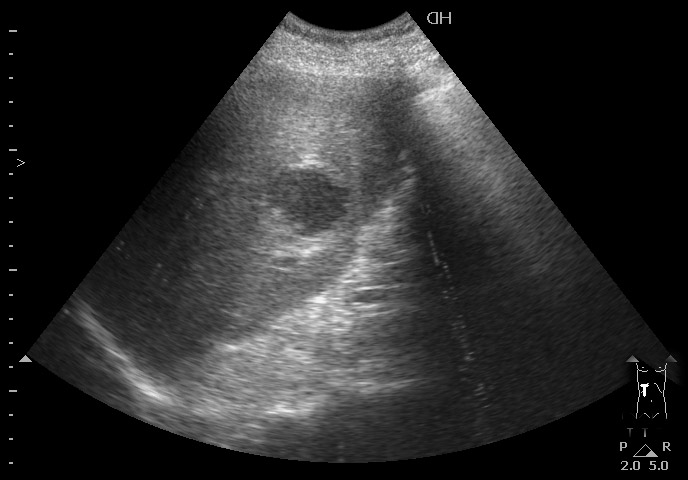

#2

10-04-09-145915_2903_201004.jpg

Типичная картина ##1-4:

Гипоэхогенное неоднородное округлое образование, окруженное эхогенным "демаркационным валом"

измененной паренхимы печени.